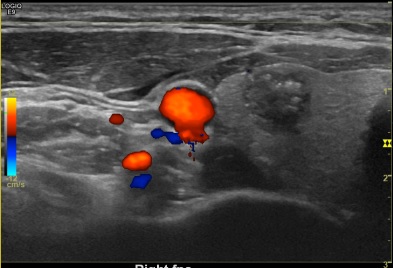

상기환자  검진차 갑상선 초음파 원하신 30대중반 여성분으로 의심스러운 갑상선 우엽 결절 세포검사진행후 갑상선암으로 진단되었습니다